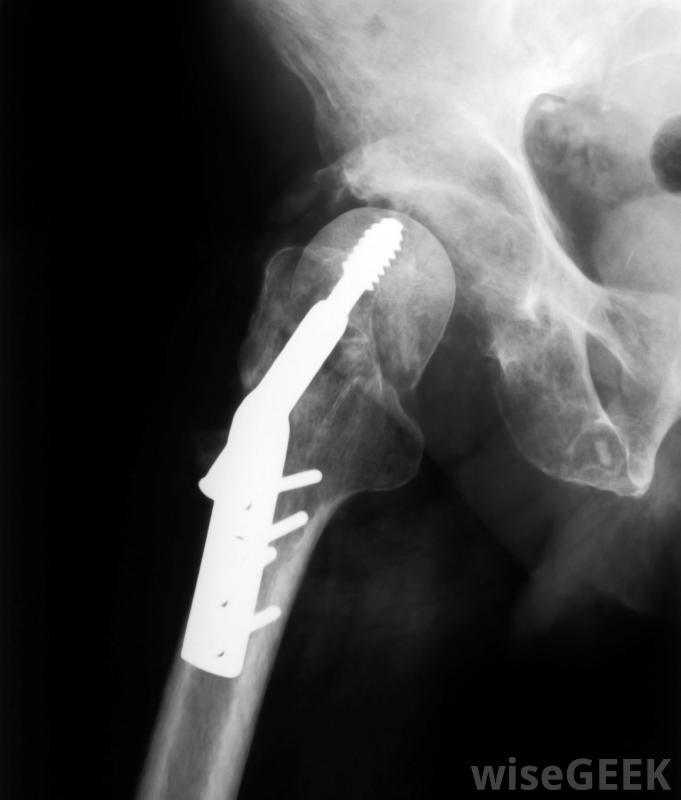

刚接受髋关节修复或置换的人通常会被给予低分子量肝素,以降低他们发生血栓的风险。

低分子量肝素也可用于高危凝血患者的预防性治疗,包括接受髋关节或膝关节置换术的患者和卧床的患者。在某些类型的心脏病发作后和一些心脏手术中也使用低分子量肝素。